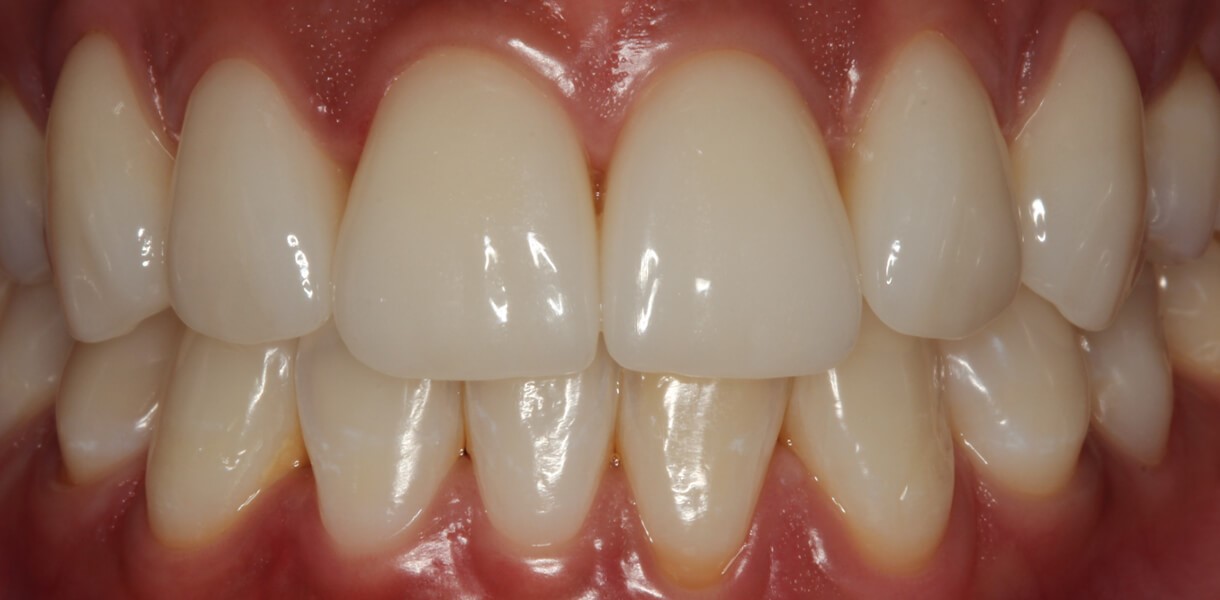

Beeinträchtigungen beim Essen, Geschmacksempfinden, Sprechen und Lachen durch schlechtsitzenden Zahnersatz müssen dank modernster Implantologie nicht mehr hingenommen werden: Den Wunsch nach einem strahlenden Lächeln können wir unseren Patienten und Patientinnen, die unter zahnlosen Ober- und/oder Unterkiefern leiden, mit dem All-on-6 und All-on-8 Behandlungskonzept in unserer Zahnarztpraxis erfüllen. Das Konzept beruht darauf, an 6 Implantaten im Unterkiefer bzw. 8 Implantaten im Oberkiefer hochwertigen Zahnersatz aus Keramik zu befestigen, der den höchsten Anforderungen an Ästhetik und Funktionalität entspricht.

Bildquelle: ©GZFA Suchen Sie einen neuen Zahnarzt in München für natürlichen, funktionellen und schönen Zahnersatz?

Um einen komplett zahnlosen Oberkiefer mit dem All-on-8 Konzept zu versorgen, benötigt man für festsitzenden Zahnersatz insgesamt 8 Implantate, die im Kiefer verteilt werden. Sofern es sich um herausnehmbaren Zahnersatz handelt, reichen 6 Implantate aus. Damit gehören wackelige Prothesen und Einschränkungen beim Kauen, Sprechen und Lachen der Vergangenheit an. Nach der mehrmonatigen Einheilzeit kann bedenkenlos wieder alles konsumiert werden – ohne Geschmackseinbußen durch Gaumenplatte und Haftcreme. Die Implantate verhelfen außerdem zu einer stabilen und knochenerhaltenden Versorgung mit ästhetisch schönem Zahnersatz aus Zirkonvollkeramik. Von echten Zähnen ist dieser hochwertige Zahnersatz nicht mehr zu unterscheiden, was gesunde und jugendliche Ausstrahlung verleiht.